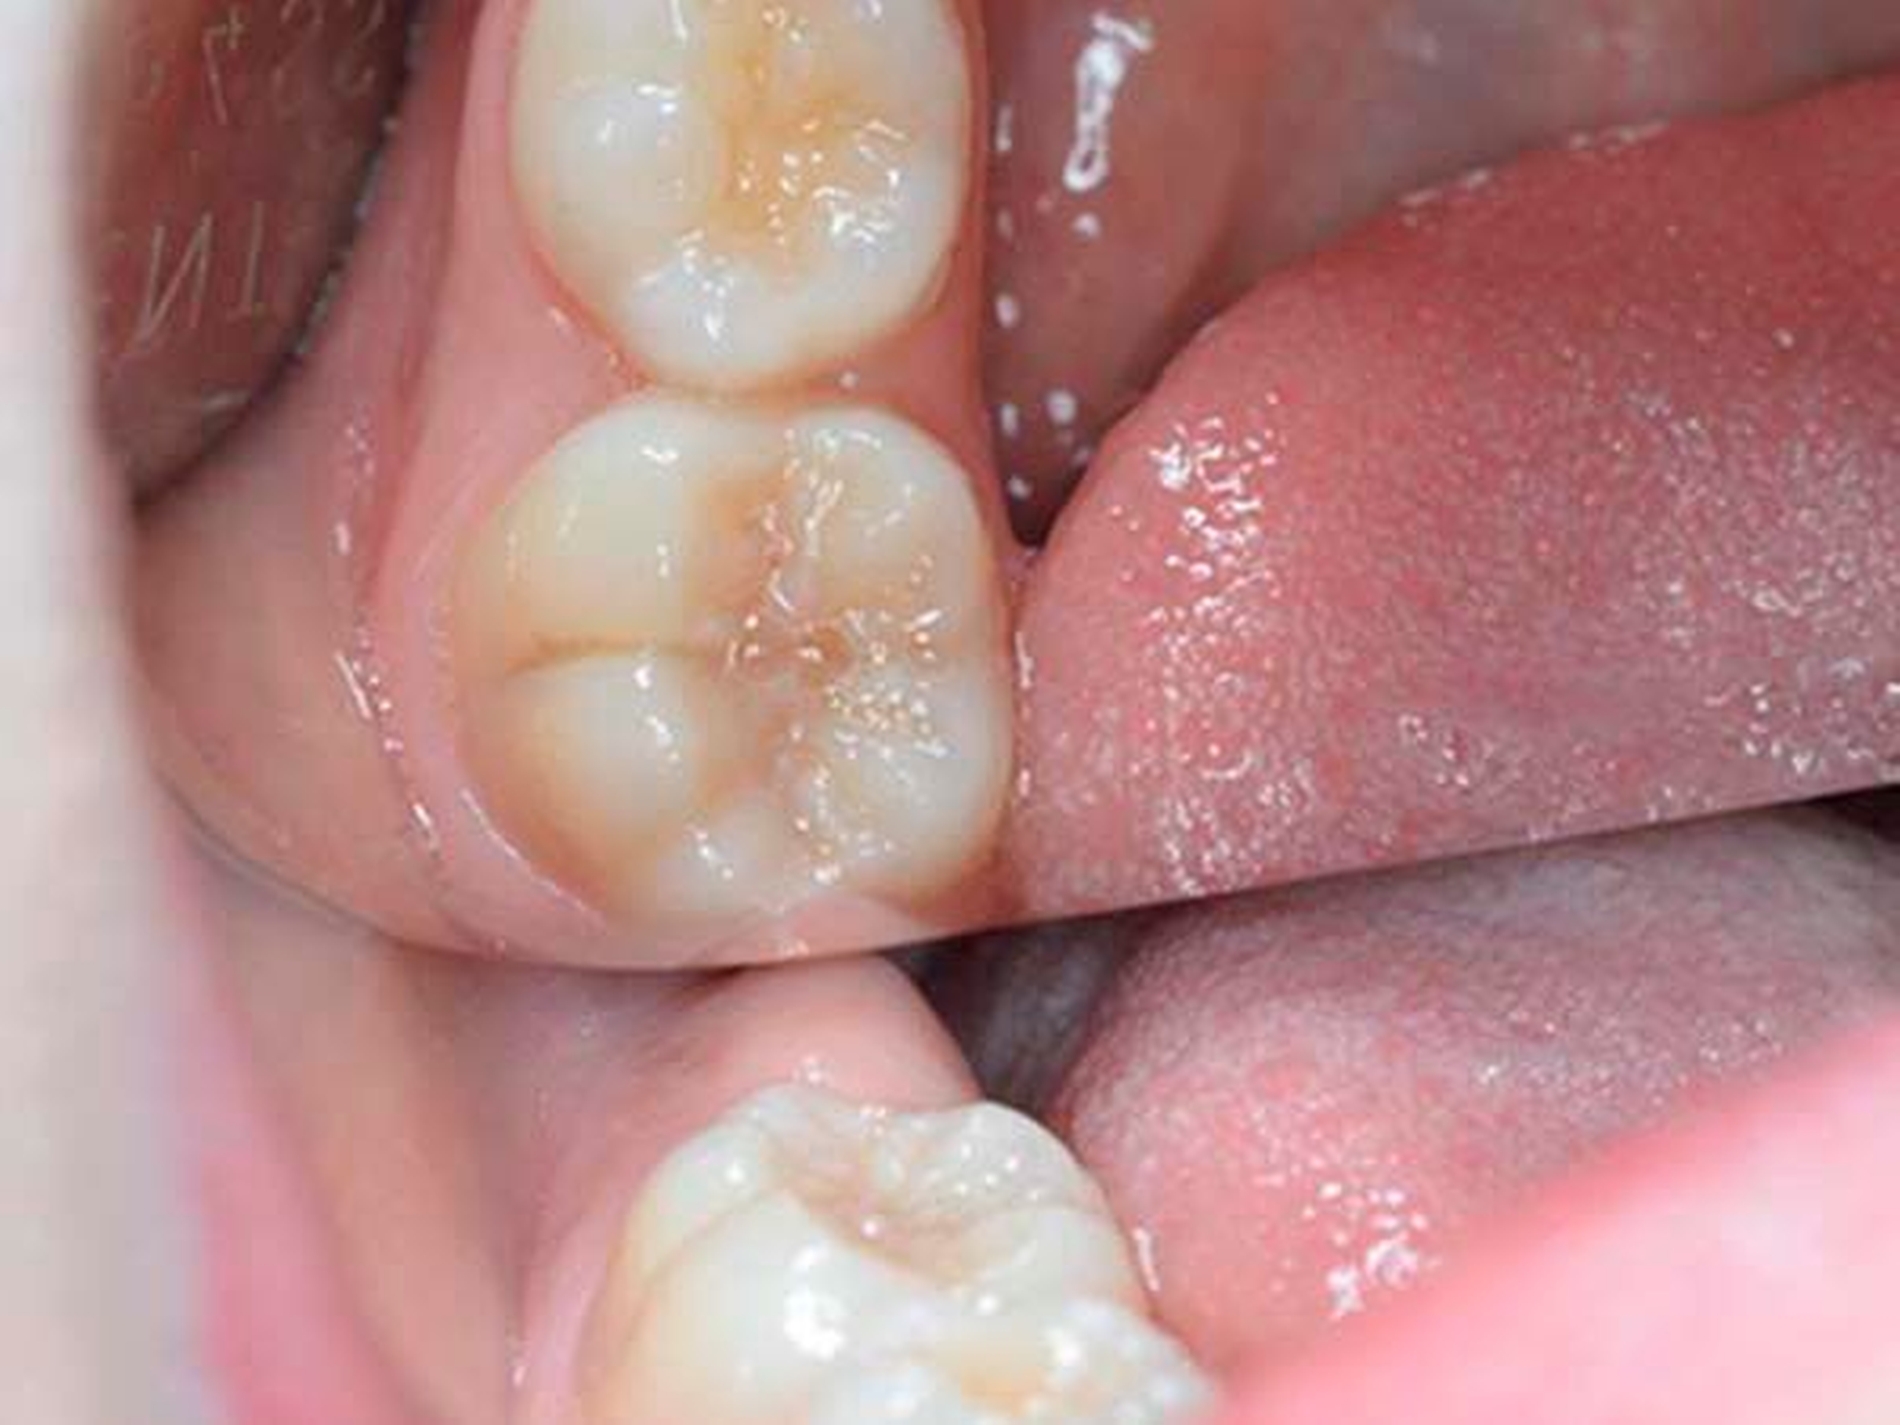

Verschiedene Theorien, wie zum Beispiel eine Antibiotikagabe während der Schwangerschaft, Bisphenol-A-Belastungen, Dioxine und Furane aus der Umwelt, ein bestehender Vitamin-D-Mangel und auch Infektionen mit Windpocken wurden als Ursache dafür diskutiert, dass Kinderzähne - vorwiegend die Sechsjahrmolaren oder die Schneidezähne - sich nicht normal entwickeln, sondern dass der Schmelz weich oder gar bröckelig ist und dem Zahn keinen Schutz bietet. Diese Zähne sind dann sehr empfindlich, die Kinder haben Schmerzen und die Zahnärzte ein Problem. Das Aufmacherbild zeigt einen zehnjährigen Patienten: Zahn 26 ist deutlich verfärbt mit hypomineralisierter Zentralfissur.